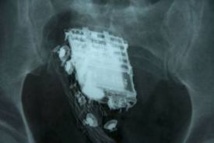

COLOMBO, 08 fév 2013 (AFP) - Un détenu sri-lankais qui espérait soustraire un portable à la fouille de sa cellule en le dissimulant dans son rectum a été confondu lorsque le téléphone a sonné, a-t-on appris vendredi de source médicale.

L'homme de 58 ans, condamné à 10 ans de prison pour vol, a été admis à l'hôpital de Colombo où les médecins ont récupéré l'objet.

"Malheureusement pour lui, le téléphone a sonné au mauvais moment et c'est comme ça que les gardes ont su qu'il avait un téléphone à cet endroit", a-t-il expliqué